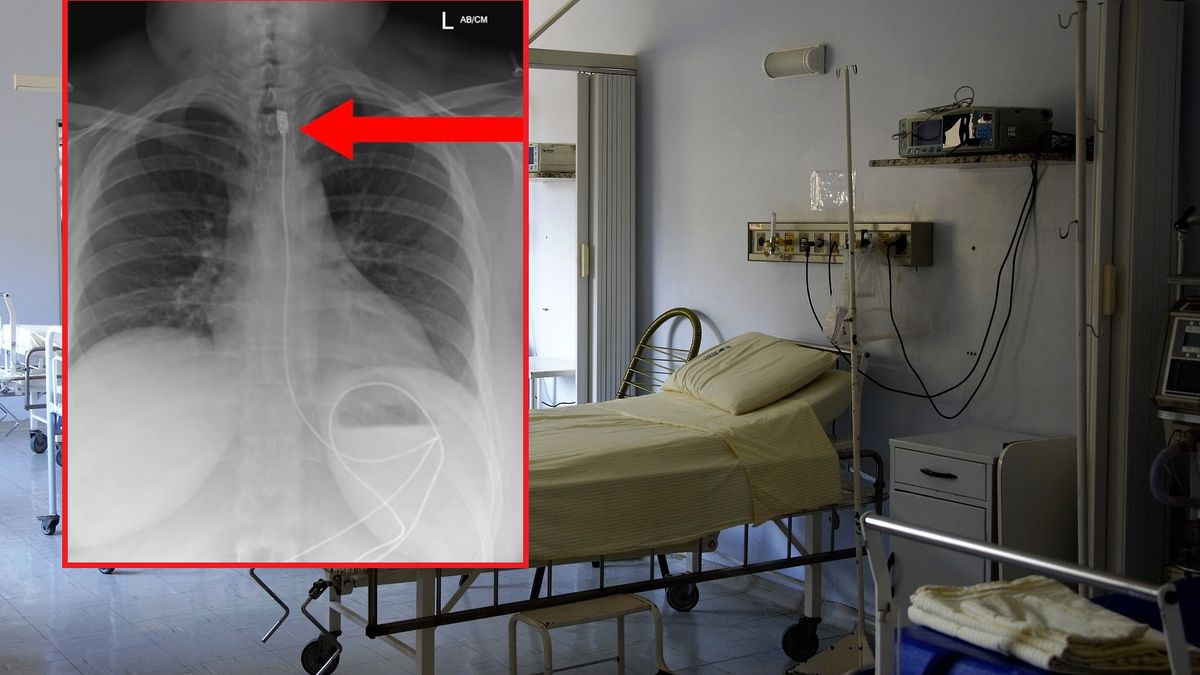

Na profilu "Gotowi Do Ratowania" pojawiła się zaskakująca informacja o nietypowym przypadku medycznym. Do szpitala trafiła kobieta, która połknęła kabel od ładowarki do telefonu. Zrobiła to w pełni świadomie.

Przypadek przedstawia kobietę, która połknęła pond metrowy przewód ładujący (zasilający) do iPhone'a. Kobieta wezwała Zespół Ratownictwa, dopiero po tym jak zaczęła odczuwać duszności (wrażenie duszności) spowodowane umiejscowieniem górnej części przewodu w jej przełyku - czytamy w poście.

Pacjentka bez miała żadnych powikłań. Została wypisana ze szpitala po szybkiej interwencji chirurgów, którzy usunęli przewód. Połknięcie takiego obiektu nie było przypadkowe. Kobieta zadziałała celowo i najprawdopodobniej cierpi na Zespół Pica.